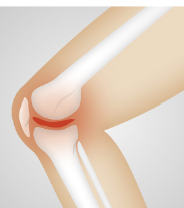

2. 무릎 염증: 무릎 관절염은 관절에 염증을 일으키기도 합니다. 염증은 무릎이 붓고 따뜻하고 붉어지는 현상을 말합니다. 염증은 감염이나 손상 때문에 일시적으로 발생할 수도 있지만, 만성적으로 지속되면 관절염의 징후일 수 있습니다. 염증은 통증과 함께 운동장애를 악화시킬 수 있습니다.

4. 무릎 변형: 무릎 관절염이 심해지면, 무릎의 모양이나 위치가 변할 수 있습니다. 변형은 연골이 마모되어 관절 간격이 좁아지거나, 연골 조각이 관절 안에 남아서 부정교합을 일으키거나, 인대나 근육이 손상되어 관절의 안정성이 떨어지는 것 등으로 발생합니다. 변형은 보통 O자 다리나 X자 다리와 같은 형태로 나타나며, 보행 시에 통증이나 운동장애를 심화시킵니다.